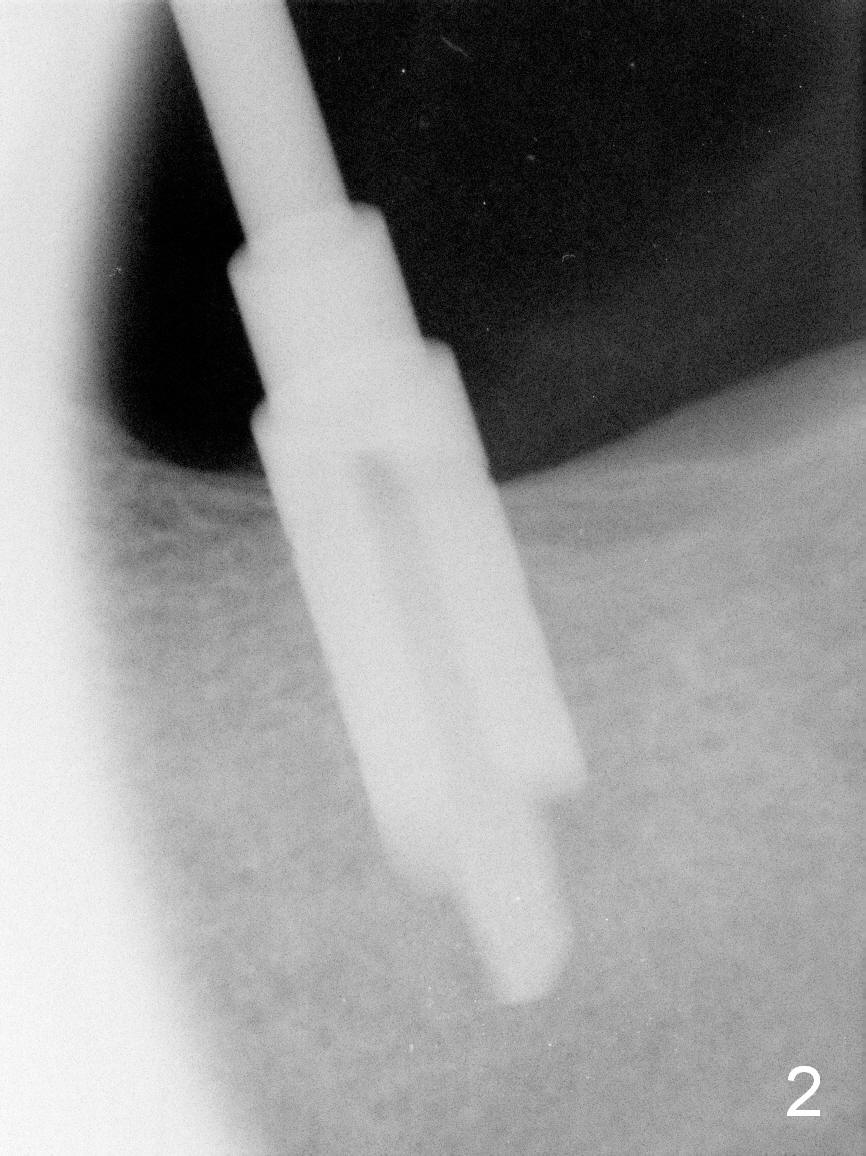

Implant Placed for Opposing Tooth Intrusion

A 4.5x8 mm Bicon implant is placed (Fig.1-3) with intent to intrude the supraerupted opposing tooth once a provisional is fabricated. Now it is 5 months postop. In spite of poor implant position, the abutment or the crown has not become loose with increased bone density around the implant 2 years 3 months post cementation (Fig.4: *). Guide could easily overcome the deficiency.